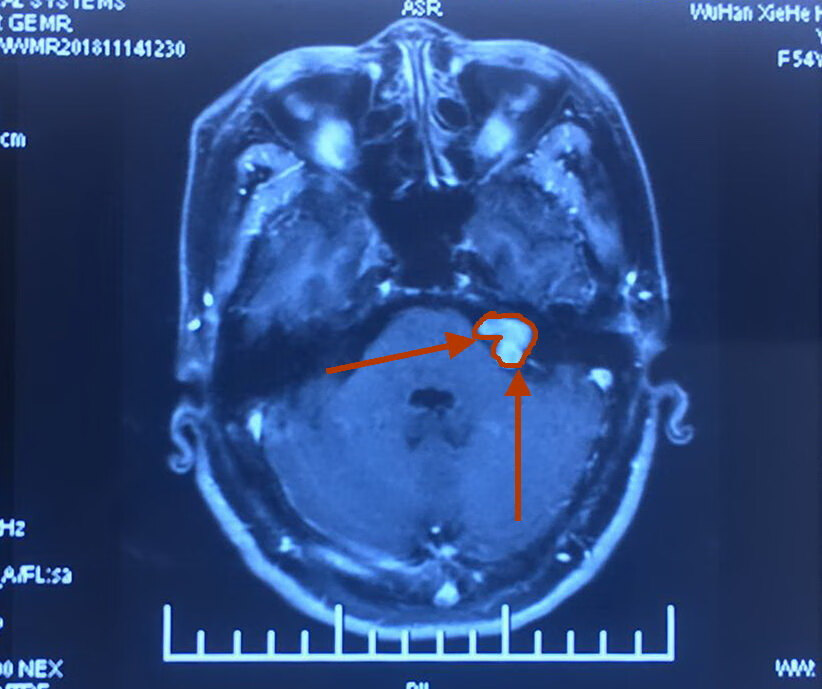

她,45岁,左耳失聪三年。经过核磁共振检查发现左侧桥脑小脑角区占位性病变,考虑听神经瘤。

肿瘤大小1.8cm。

术前影像如下:

术前内听道CT显示左侧内听道口较对侧明显扩大,呈喇叭口状。